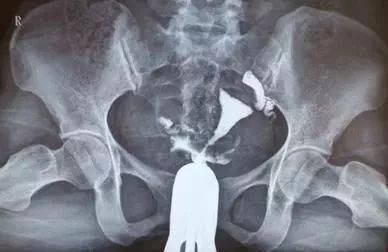

輸卵管造影是輸卵管粘連的一種檢查,做了輸卵管造影之后的女性,一定要遵循醫(yī)囑。

輸卵管檢查的時(shí)間,不能過早,也不能過晚,一定要選擇適合的時(shí)間檢查。輸卵管檢查的最最佳時(shí)間,一般是月經(jīng)干凈后的3到7天內(nèi),最遲不能延遲到月經(jīng)干凈后的10天。

輸卵管檢查,對檢查的時(shí)間要求也是很高的。 要是檢查的時(shí)間過早的話,子宮內(nèi)膜尚未完全修復(fù),容易造成感染或者子宮內(nèi)膜異位癥的發(fā)生。

要是檢查的時(shí)間是在排卵期的話,容易造成輸卵管內(nèi)口假性阻塞,同時(shí)易致術(shù)中及術(shù)后子宮流血。所以女性朋友要引起注意。

4)造影時(shí)間應(yīng)在產(chǎn)后6個(gè)月,診刮及人流等宮腔操作手術(shù)后6周以后,正常月經(jīng)干凈后3-7天內(nèi)進(jìn)行。